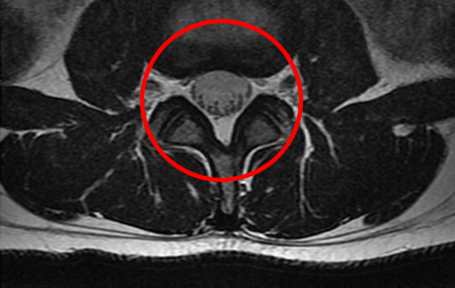

협착증 한방치료로 신경압박이 풀리는 눈에 보이는 증거가 있습니다.